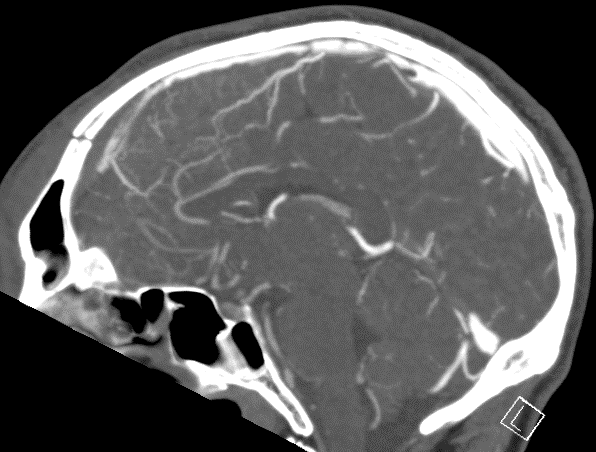

CASE 2 -A 54-year-old man walks into emergency 3 hours after a 150kg plank of wood fell on his head. He has obvious external signs of head injury and a cracking headache, however, neurologically he is intact. A CT head scan is performed

EXPLANATION –There is a depressed right parietal bone fracture with underlying pneumocephalus (indicates an open skull fracture) and a small subdural hematoma.

- Overlying this there is a scalp hematoma.

- There is also a non-displaced fracture in the frontal bone. This fracture crosses the midline and probably has injured the anterior aspect of the superior sagittal sinus.

- Tears of the dural venous sinuses may cause an extradural hematoma (EDH), as in this case. The hematoma is seen external to the compressed superior sagittal sinus.

Extradural bleeds (EDH) are located between the outer layer of dura and endosteal layer of skull. Like in this case, they are usually associated with calvarial fractures.

- They typically demonstrate biconvex or lentiform shape and are limited by sutures as periosteum is attached at the sutures limiting spread of the bleed.

- The source of bleed is arterial in origin, from a middle meningeal artery as opposed to venous in subdural bleeds.

- Up to 10% of EDH are due to venous bleeding, follow the laceration of a dural venous sinus, as we see in this case.

- There is often displacement of the sinus away from the underlying bone. There are three locations characteristic of venous EDH; the vertex, anterior middle cranial fossa and the occipital posterior fossa.

- Hypodense areas within a bleed likely represent unclotted blood suggesting active bleeding.

- As these bleeds are venous, there is not the same urgency for decompression in theatre. In fact, this patient was managed conservatively as operative intervention poses a risk of further damage to the venous sinuses.